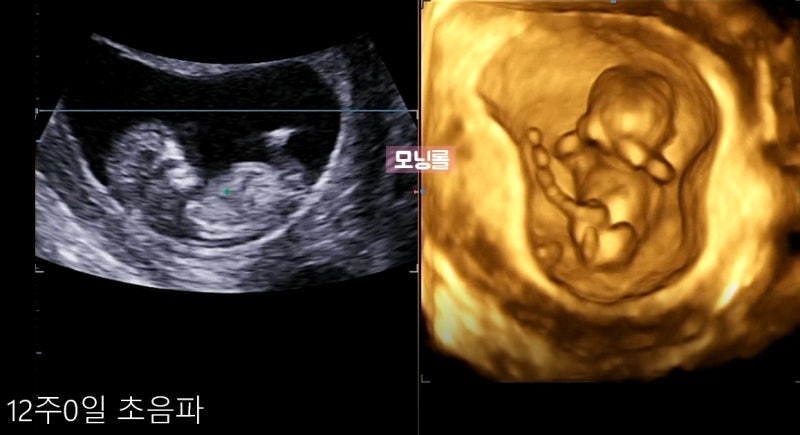

1.1차 정밀초음파&통합선별검사 임신 12주차는 중요한 시기로 아이가 많이 커져 배 초음파가 가능해져 1차 정밀초음파검사와 통합선별검사를 하게 됩니다.

정밀초음파는 1차(10~13주), 2차(20~21주)에 시행되는데, 1차 정밀초음파 검사: 태아목 투명대(NT) 두께 측정으로 태아의 염색체, 심장에 이상이 있는지 확인합니다.보통 2.5mm 미만이 정상입니다(목투명대란 아기를 둘러싼 차양막에서 목까지의 빈 부분입니다.)